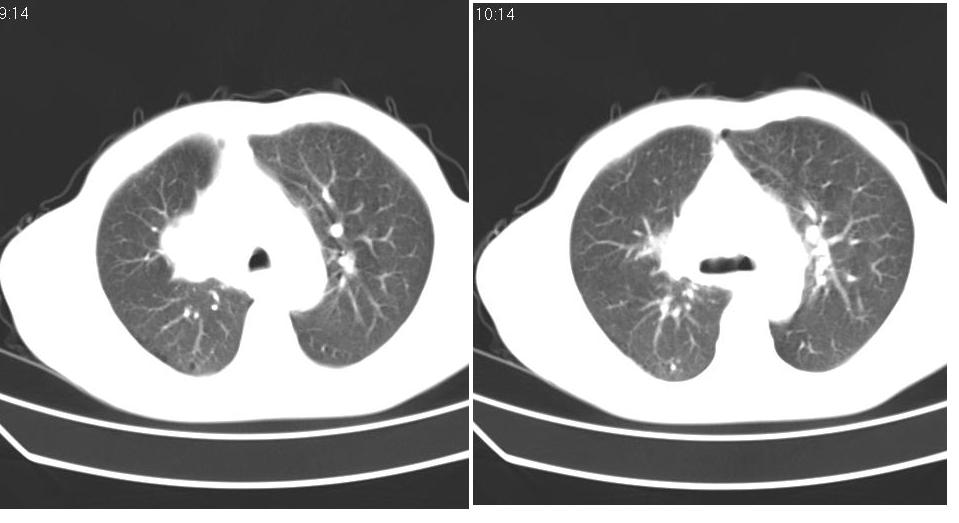

男 58岁 咳嗽,无明显不适.

中央型肺癌伴有右肺上叶不张。

右侧肺门肿块,右上叶不张,右上胸廓塌陷,气管纵隔右移,纵隔内有些小淋巴结,考虑中央型肺癌,作个支气管纤维镜取个病理吧,鳞癌的可能性大

右肺上叶中央型ca,右上叶支气管起始部变狭窄,致右肺不张,纵隔及腋窝淋巴结肿大,请结合纤维镜检查.

右侧肺门肿块,右上叶不张,右上胸廓塌陷,气管纵隔右移,纵隔内有些小淋巴结,考虑中央型肺癌伴右肺上叶不张,作个支气管纤维镜取个病理吧.